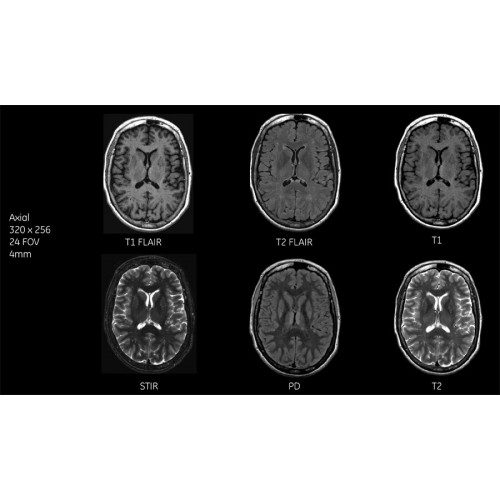

Детализация изображений

Система SIGNA Pioneer воплощает поразительные достижения в области визуализации. Передовая технология Total Digital Imaging (TDI) позволяет добиться большей четкости изображений и на четверть повысить соотношение сигнал/шум.